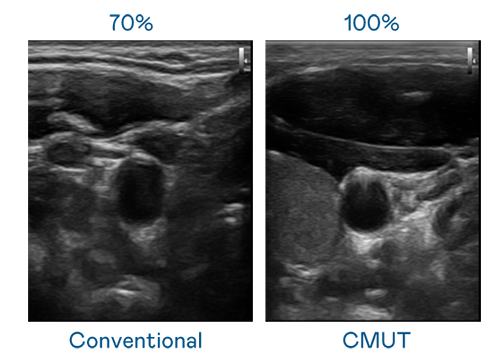

CMUT 技术是一种用电容式微机电元件来产生超音波讯号的技术。与传统 PZT 压电式技术相比,CMUT 频宽增加 30%,更宽频的超音波讯号让影像解析度大幅提升,是实现高影像品质医疗超音波扫描、促进精准医疗发展的关键技术。

大频宽带来超清晰影像

超音波影像的解析度高低,首先取决于探头能发出的讯号频宽。韦德1946 CMUT 可提供高清晰的超音波讯号,提供高频宽、高灵敏度、影像纹理细节更高的超音波影像,协助医护人员缩短影像判读时间及利用精准的医疗影像进行诊断。